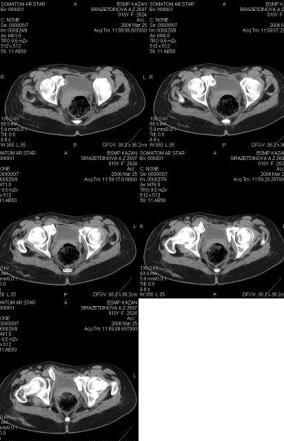

Предоставляю срезы. Если пациентку функционально ничего не беспокоит, стоит ли навязывать ей лечение.

Предварительный диагноз- посттравматическая вертикальная нестабильная деформация таза II степени, неправильно срастающийся перелом боковой

массы крестца справа, правой лонной и седалищной костей, застарелый разрыв лонного сочленения.

Для уточнения диагноза ниеобходимы обзорные рентгенограммы таза (прямая и inlet), Кт срезы на уровне переломов для определения степени сращения и решения вопроса о методе оперативного восстановления анатомии (делать ли остеотомию, низводить ли задние отделы), ни о какой "остеотомии выступающих отломков" тем более у девочки 18 лет речи быть не может.

При более детальном распросе, наверное, удастся обнаружить и другие жалобы, либо они появятся при увеличении нагрузок. Как представляется, задачей лечения будет являться восстановление целостности и стабильности тазового кольца. Оптимальным вариантом может быть низведение левой половины таза, затем реконструкция передних отделов. Варианты выполнения репозиции и фиксации - тема отдельного разговора.